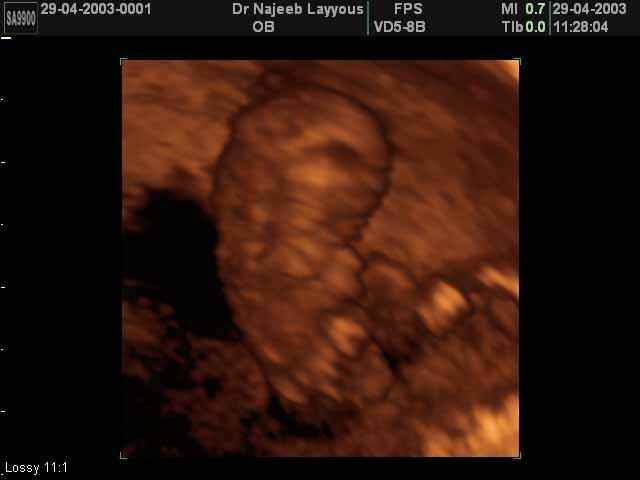

- First Trimester Ultrasound Photos

3D First Trimester Ultrasound Scan Photos ( Early Pregnancy Ultrasound Photos ) | Dr N Layyous